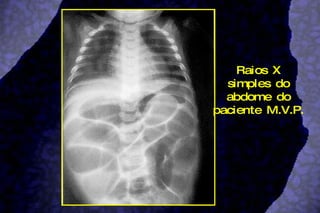

Íleo Paralítico (íleo infeccioso) Atonia do intestino delgado e cólon por processo infeccioso grave a distância (broncopneumonia, enterite, septicemia) ou por distúrbio metabólico (gastroenterocolite)  Acomete principalmente RN e lactentes Confusão diagnóstica com abdome agudo Clínica Toxemia e outros sinais devido a doença de base Excepcionalmente vômitos (claro) Discreta rigidez da parede abdominal Timpanismo generalizado Ausência de ruídos hidroaéreos Raios X simples:  Alças intestinais uniformemente distendidas, paredes finas e calibres semelhantes  Ausência de nível líquido A regressão do quadro é conseguida com o tratamento da infecção e repouso do tubo digestivo até a recuperação do trânsito intestinal

Raios X simples do abdome do paciente M.V.P.

Raios X simplesdo abdome do paciente M.V.P.